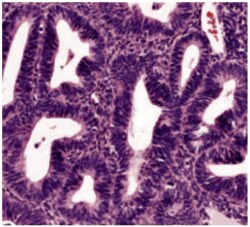

Histological classification of endometrial hyperplasia

Endometrial hyperplasia is further classified as simple or complex, with or without atypia. This classification system is based on the complexity and crowding of the glandular architecture.1

Endometrial hyperplasia is broadly defined as an excessive cellular proliferation leading to an increased volume of endometrial tissue. It is characterised by an increase in the endometrial gland-to-stroma ratio greater than 1:1.1